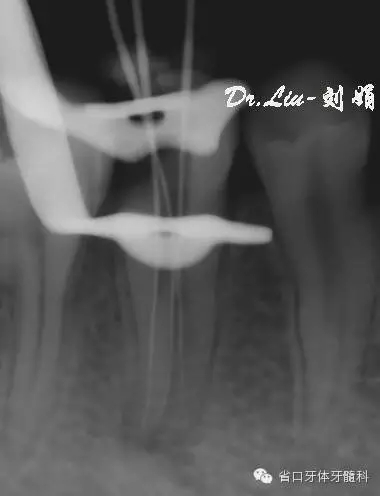

拍攝CBCT顯示為45根管下段分為3條根管

圖2/3:拍攝CBCT顯示45為3個(gè)根管。